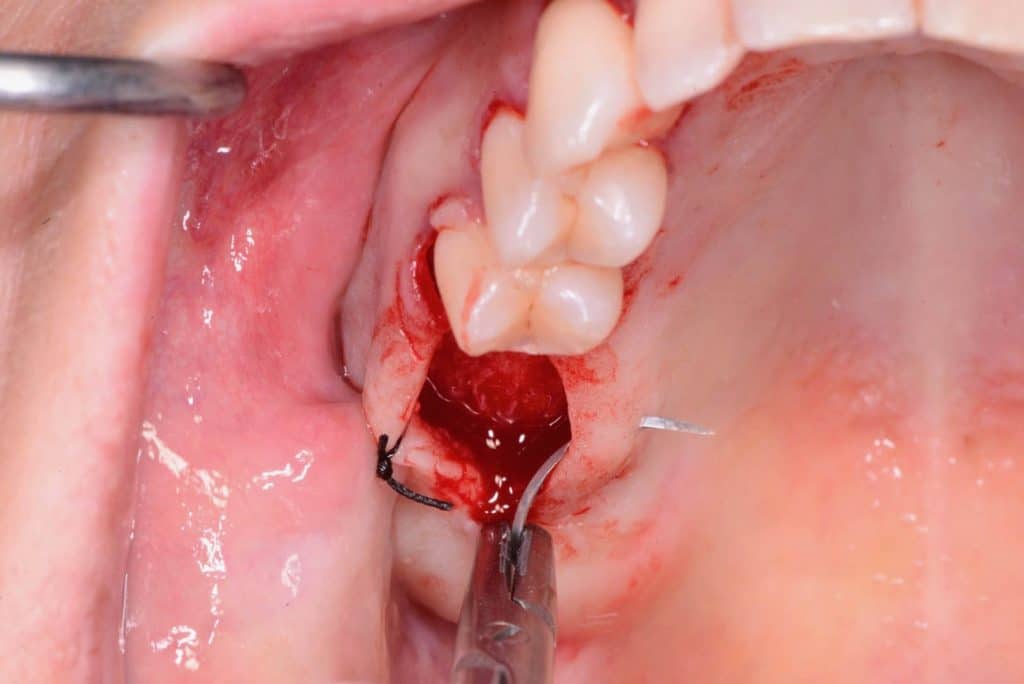

Two 8mm Straumann Wide-Neck have been inserted. After inserting a healing abutment with a height of 2 mm, a detached stitches suture was made. Good planning allowed me to be precise with the incision, and only 2 stitches have been necessary.

one week follow-up